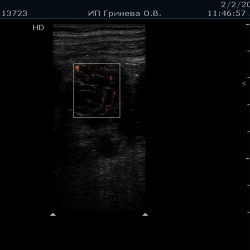

Мужчина, возраст 60 лет, пришёл на обследование после того, как заметил небольшое уплотнение у себя на шее. Пальпаторно образование мягкой консистенции, легко смещаемое, безболезненное.При...